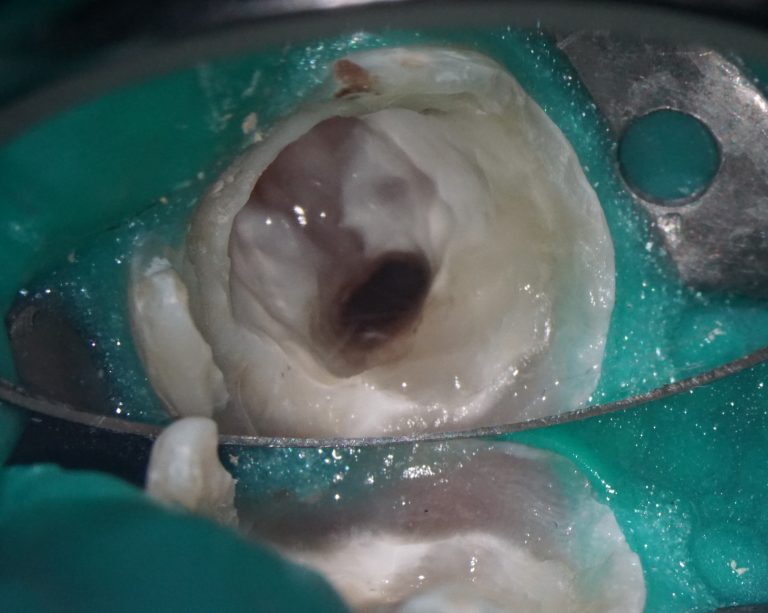

Extracting upper third molars can be difficult, if they are impacted and in contact with the maxillary sinus. Diagnocat AI will help you carefully plan your procedure, minimizing the risk of possible complications.

Teeth 18 (Universal 1) and 28 (Universal 16) were removed with minimal surgical trauma and without causing damage to the maxillary sinuses.